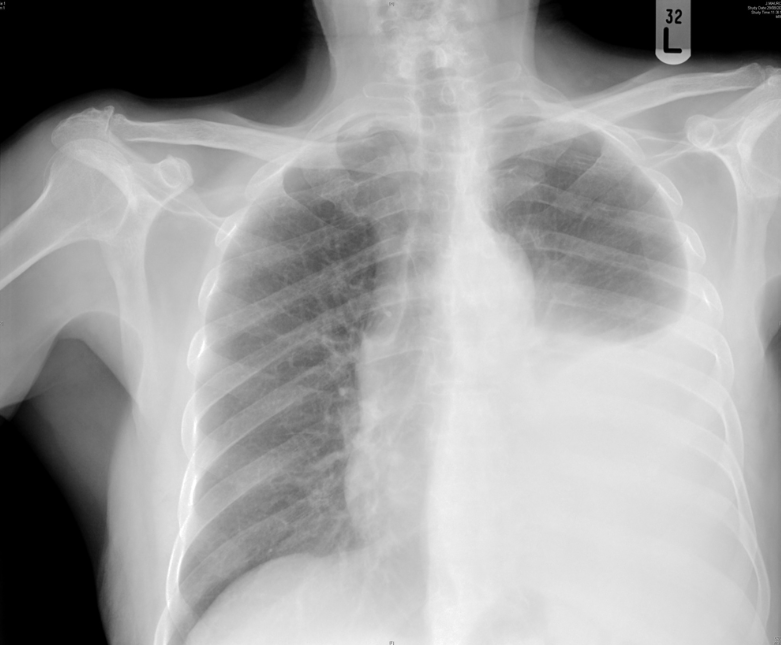

Left pleural effusion - meniscus seen